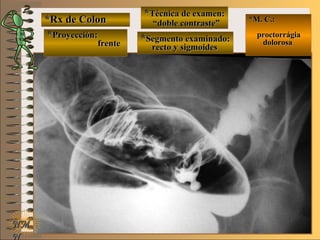

*Rx de Estómago*Rx de Estómago

**Proyección:Proyección:

**Técnica de examen:Técnica de examen:

A-A-

B-B-

C-C-